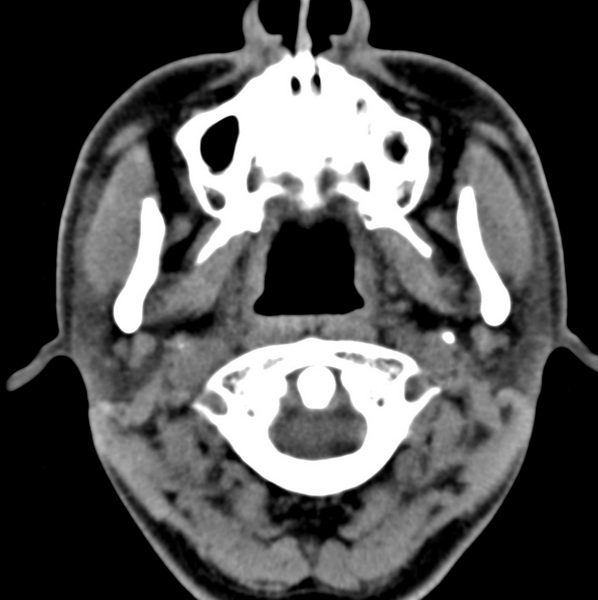

男、31、鼻咽部肿瘤放疗后请帮忙看看。

效果好,右侧破裂孔扩大,局部骨质缺损,为颅底骨质破坏。

1)鼻咽部肿瘤侵犯颅底放疗术后改变。2)左侧蝶窦炎。

咽后壁增厚,左侧咽鼓管隆突增大、咽鼓管咽口变浅,同侧咽旁间隙较窄。右侧颅底骨质破坏?为什么不在同一侧?

鼻咽部肿瘤侵犯颅底放疗术后改变.